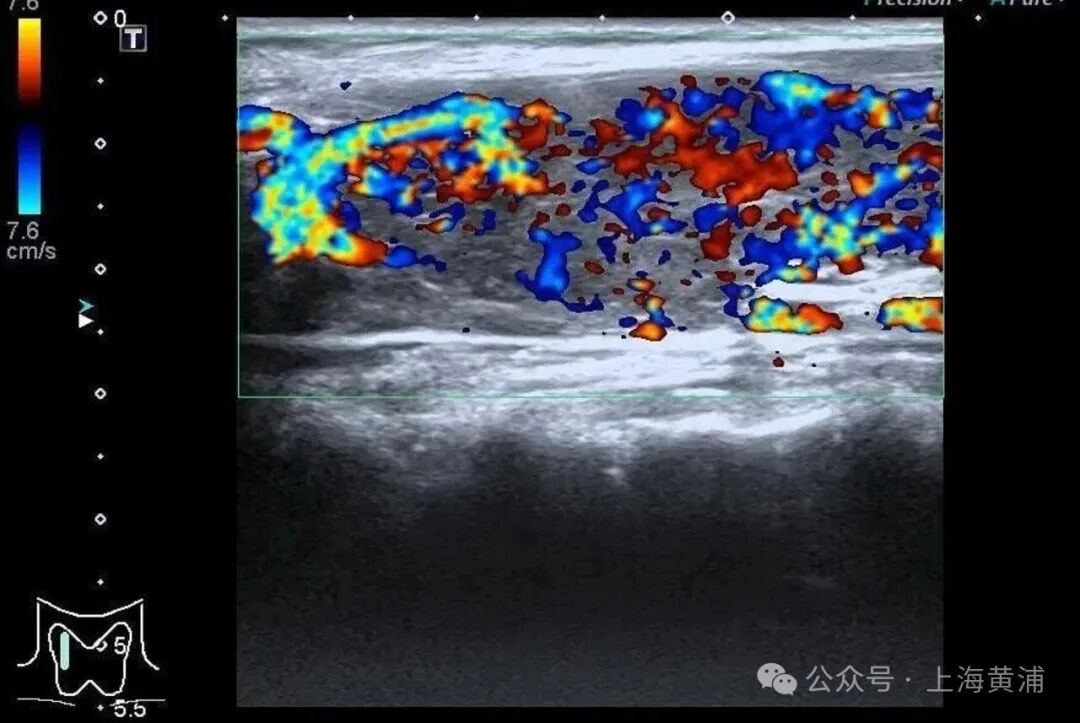

甲状腺功能稽查中,游离T3高达20.83 pmol/L (平方值3.5 - 6.5pmol/L),游离T4高达88.42 pmol/L(平方值11.5 - 22.7pmol/L),这两项中枢激素皆跨越平方上限数倍,而本应调控它们的促甲状腺激素(TSH)却着实测不出来,这明确阐述了陈女士患有极其严重的甲状腺毒症。腹黑超声终端不异庇荫乐不雅,射血分数仅有40%(平方应高于55%),这意味着腹黑泵血智商大幅下跌。